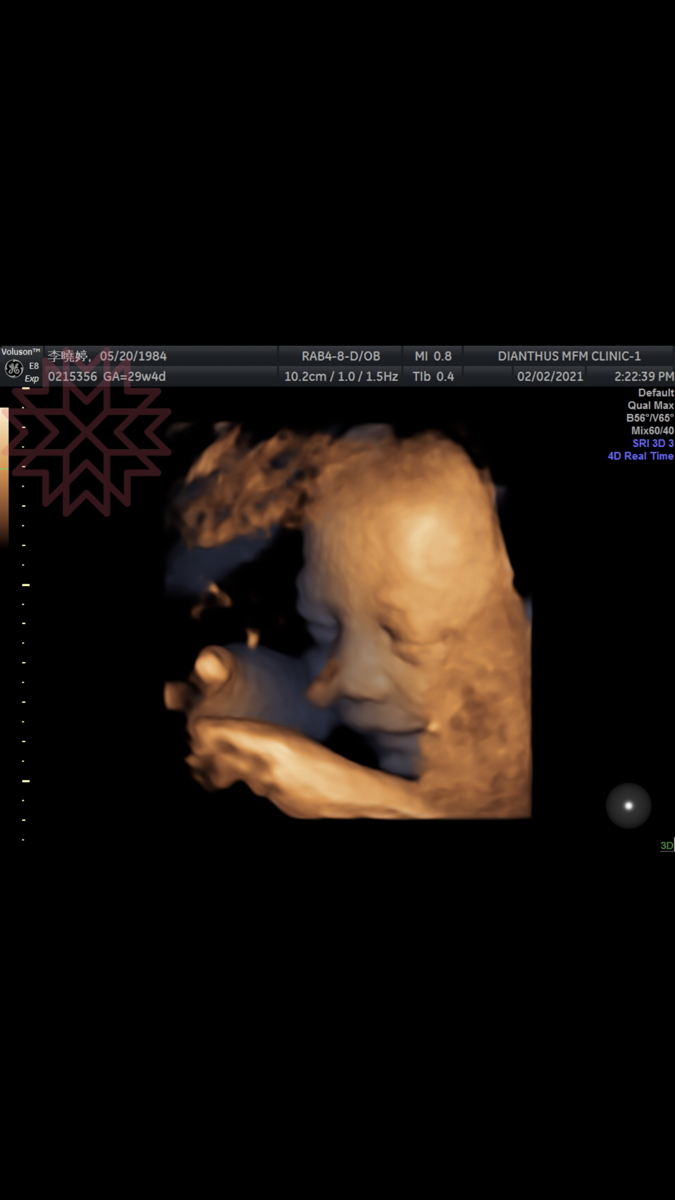

下半年來了個驚喜,原本是想,疫情走完上半年,最壞、最不確定的狀況已過,下半年會否極泰來,生活工作恢復往常,沒想到懷了疫情寶寶,預產期110年4月。心中當然是開心的,但在初期整整4個月不想動,曾經還有幾次早會時,跑到廁所一關上門,就像噴泉式的吐了整個馬桶,之後很悲情的用衛生紙把週圍清乾淨。仔細看了那四個月的行事曆,幾乎沒做什麼事……坦白說,可以理解當時的狀態,為什麼4個月什麼事都不想做,在2年前有胚胎萎縮過,有點害怕生命殘忍的淘汰機制,不知道這一次是否能夠順利過每個關卡。當我們不斷地從螢幕看到藍天充滿生命力的四肢、 聽到他強而有力的心跳時,既覺得不可思議,又緩慢地認知到自己真的懷孕的事實。

8個月29週藍天,在笑什麼呢?